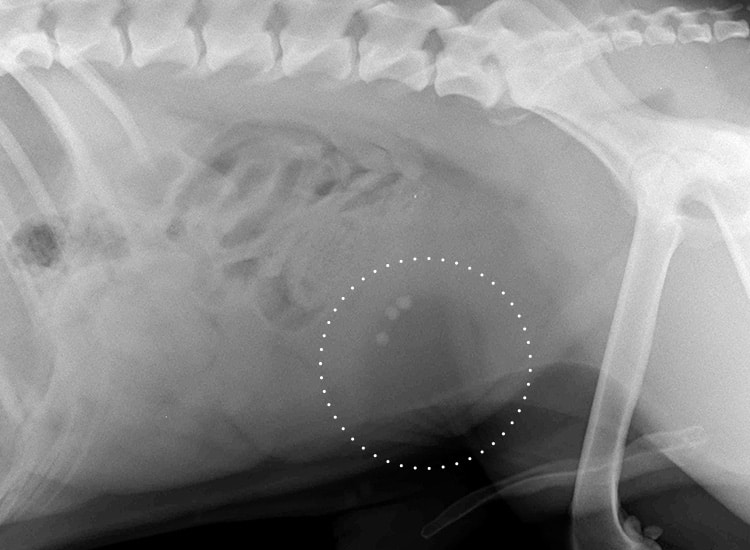

Le vétérinaire peut avoir recours à la radiographie afin d’effectuer son diagnostic. Lors de cet examen, la présence de calculs dans la vessie du chien peut être mise en évidence sous forme de petites opacités rondes ou irrégulières, visibles dans la région vésicale. Ces formations minéralisées apparaissent plus denses que les tissus environnants. La radiographie permet d’en déterminer le nombre, la taille et la position, mais certains types de calculs, moins visibles aux rayons X, peuvent nécessiter un examen complémentaire, comme une échographie, pour confirmer le diagnostic et évaluer l’état de la vessie.

Radiographie abdominale révélant des calculs urinaires dans la vessie d’un chien